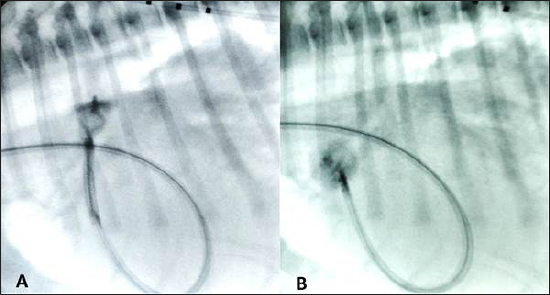

Anesthesia was induced and maintained as previously described (Bagardi et al., 2022) and perioperative intravenous amoxicillin (22 mg/kg) was administered. The dog was placed in left lateral recumbency on the fluoroscopy table, the right jugular vein was surgically isolated by a cut-down technique, and an 11 Fr, 10 cm long introducer vascular sheath (Pinnacle Peripheral Introducer Sheath, Terumo Medical Corporation, Somerset, NJ) was inserted into the jugular vein. A 4 Fr, 65 cm long diagnostic catheter (Berenstein Hockey stick tip catheter, Infiniti Medical, Huddersfield, UK) was then inserted into the jugular vein along with a preplaced straight tip hydrophilic 0.035″, 150 cm long guidewire (Terumo Radiofocus® Glidewire, Terumo Medical Corporation, Somerset, NJ). The guidewire and catheter were passed, under fluoroscopic guidance, through the right ventricle into the pulmonary artery and through the PDA in a retrograde manner until the tip of the catheter reached the descending aorta. After removing the guidewire, an angiographic study using 3 ml of iohexol (240 mg/ml), manually injected, was performed, showing the morphology of the PDA (length: 9 mm, maximal ampulla width:10.4 mm, minimal PDA diameter at the ostium: 5.4 mm). Following angiography, a standard stiffness 0.035″, 175 cm long J-tip guide wire (Medtronic Angiographic PTFE Rosen Wire, Medtronic Vascular, Danvers, MA) was advanced into the descending aorta and the diagnostic catheter was removed. A 7 Fr × 40 cm guiding sheath with a 2.54 mm inner diameter (Flexor Balkin KCFW-7.0-38-40-RB-BLKN-HC with Check-Flo Valve, Cook Medical Inc., Bloomington, IN) was advanced over the guidewire into the descending aorta to serve as a delivery sheath, and the guidewire was removed together with the dilator. A 16 mm AVPII was positioned via the delivery sheath into the PDA ampulla as previously described (Bagardi et al., 2022); however, an immediate “pull-through” into the pulmonary artery occurred before deployment (Fig. 3). The device was retracted and removed. Given the PDA morphology and the failure to secure the AVPII, we chose a 12 mm Amplatzer™ mVSD occluder device with a disc diameter of both discs of 20 mm, device waist size of 12 mm, and a length of connecting waist of 7 mm. This choice was based on the fact that the larger AVPII device is 18 mm wide and, given the ease and immediacy of pulling through, we thought that a device less than 2 mm wider would not have guaranteed against a post-operative embolization, even if successfully implanted. Furthermore, the next-sized AVPII (18 mm) is twice as long as the mVSD (14 vs. 7 mm). We considered that larger AVPII devices could have obstructed the aorta or pulmonary artery, as has been described in children (Salam et al., 2022).

Fig. 3. (A) Fluoroscopic sequence after the AVP II first disc has been released engaging the aortic side of the PDA and the central part left unsheated and (B) subsequently the other second component has been deployed an immediate “pull-through” into the pulmonary artery occurred immediately after to deployment of the whole device